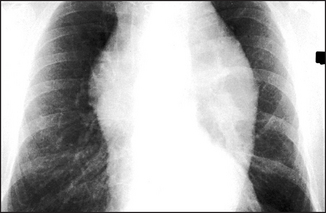

Figure 8.2 Normal chest X-ray (a) The posteroanterior view shows: (1) aortic knuckle; (2) left heart border formed by the lateral border of the left ventricle; (3) left hilum, formed mostly by the left main pulmonary artery and partly by the left upper pulmonary veins; (4) right heart border formed by the right atrium; (5) inferior angle of the scapula; (6) right basal pulmonary artery; (7) medial aspect of the left clavicle; (8) spine of the scapula; (9) right cardiophrenic angle; and (10) superimposition of the right lateral margins of the superior vena cava and the ascending aorta. (b) The lateral view shows: (11) anterior border of the trachea; (12) pulmonary vein, entering the left atrium; (13) oblique fissure; (14) left hemidiaphragm; and (15) right hemidiaphragm.

The radiological changes seen in pulmonary venous congestion, interstitial pulmonary oedema and alveolar pulmonary oedema are shown in Figures 8.3 to 8.5, respectively. Mitral valve disease is shown in Figure 8.6, while a ventricular aneurysm is seen in Figure 8.7. The characteristic notching of the inferior aspects of the ribs, due to hypertrophy of the intercostal arteries, appears in Figure 8.8, while the pulmonary plethora that is characteristic of a left-to-right shunt is obvious in Figure 8.9. Marfan’s syndrome is illustrated in Figure 8.10; and a pacemaker and defibrillators are shown in Figure 8.11.

Figure 8.9 Atrial septal defect (ASD) The most important thing to recognise is that there is pulmonary plethora indicating a left-to-right shunt. Left-to-right shunts occur in ASD, ventricular septal defect (VSD) and patent ductus arteriosus (PDA). The shunted flow causes enlargement of the main pulmonary artery and its branches. The right hilum is enlarged because of the very dilated right pulmonary artery. The left hilum is hidden by the very dilated main pulmonary artery (arrow). The ascending aorta is small (in contrast to its enlargement in PDA). The left atrium and ventricle are not enlarged, as they are in VSD and PDA.